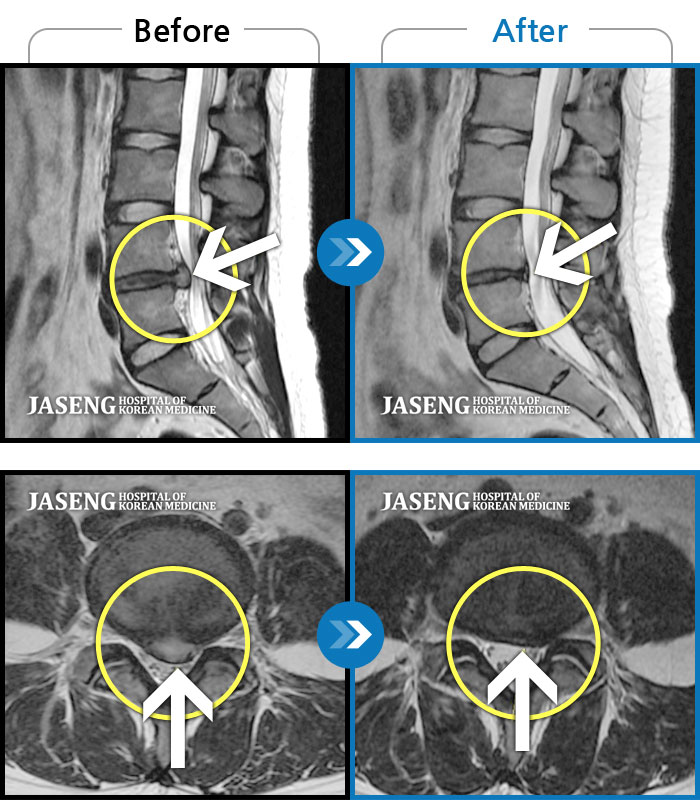

MRI 치료사례

앉았다 일어날때 통증, 허리 당김